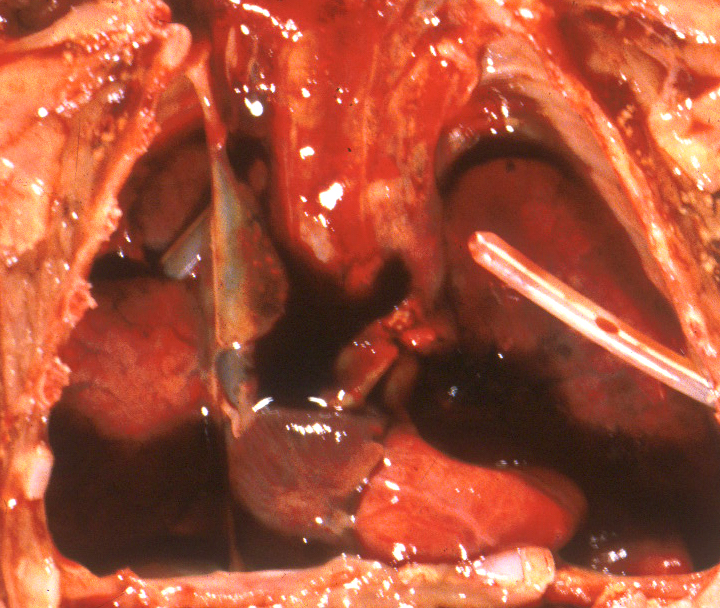

A diaphragmatic hernia is another form of mass effect, but in addition may also have a primary abnormality of lung development on the side with the hernia. Even in the normal thorax, the smaller left, compared to right, lung may be smaller because of the predominance of the heart mass in the left side of the thoracic cavity. Fluid having a mass effect is usually from a pleural effusion from anasarca due to heart failure which is termed by tradition as fetal hydrops. The causes of fetal hydrops will be presented in the obstetrical pathology chapter on fetal anomalies associated with perinatal death. A less common cause of pleural effusion is an abnormality of lymphatic drainage either from thoracic lymphangiectasia and failure of normal thoracic duct formation. Lymphatic fluid has a higher protein content than that in an effusion. An abnormality of lymphatic drainage may be associated with a mediastinal shift from asymmetric fluid accumulation (Fig 5a, b).

The lungs were not technically hypoplastic with a lung: body weight ratio of 0.02, but the amount of air way tissue was decreased.